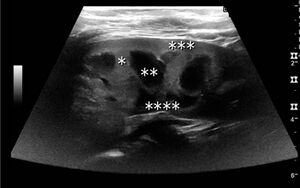

Figure 2. Normal pediatric kidney. * Column of Bertin; ** pyramid; *** cortex; **** sinus.[1]

The kidney is divided into parenchyma and renal sinus. The renal sinus is hyperechoic and is composed of calyces, the renal pelvis, fat and the major intrarenal vessels. In the normal kidney, the urinary collecting system in the renal sinus is not visible, but it creates a heteroechoic appearance with the interposed fat and vessels. The parenchyma is more hypoechoic and homogenous and is divided into the outermost cortex and the innermost and slightly less echogenic medullary pyramids. Between the pyramids are the cortical infoldings, called columns of Bertin (Figure 1). In the pediatric patient, it is easier to differentiate the hypoechoic medullar pyramids from the more echogenic peripheral zone of the cortex in the parenchyma rim, as well as the columns of Bertin (Figure 2).[1]